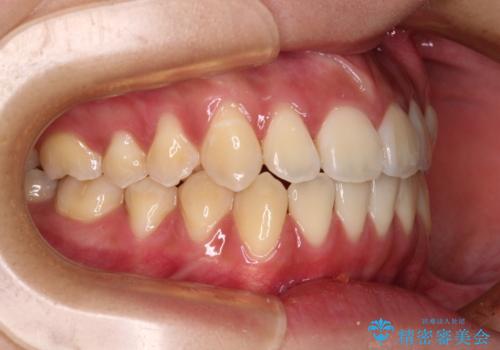

受け口と開咬を急速拡大装置とワイヤー装置で改善

- 前歯の開咬と、受け口による咬み合わせの悪さを気にして来院された患者様です。

上顎歯列が狭窄していたため、急速拡大装置により上顎骨を側方に拡大し、その後ワイヤー装置にて矯正治療を行うこととしました。